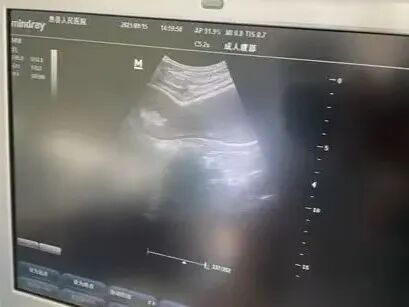

目前,传统洗胃机给患者洗胃时的压力设定、送液与出液转换都是自身控制,它会在短时间、高速度、大流量地给病人送液,高压的水流长时间反复地冲洗可以导致胃粘膜充血、溃疡,甚至出血,进而导致胃穿孔、胃破裂,洗胃液进出胃的液量以及是否达到溶解药物、毒物或食物的作用、是否将存留于胃中的药物、毒物或食物清洗干净、是否导致存留于胃中的药物、毒物或食物进入肠道等关键环节都是凭借临床经验。然而,超声引导下洗胃能观测到洗胃管是否在胃内、胃内情况,从而对胃肠减压监护。

超声引导下洗胃是指在超声设备的辅助下,通过插入胃管进行洗胃操作。超声技术能够实时观察胃内情况,确保洗胃操作的安全性和有效性。